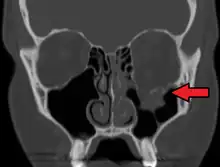

At the beginning of the 20th century, René Le Fort mapped typical locations for facial fractures; these are now known as Le Fort I, II, and III fractures (right).[7] Le Fort I fractures, also called Guérin or horizontal maxillary fractures,[14] involve the maxilla, separating it from the palate.[15] Le Fort II fractures, also called pyramidal fractures of the maxilla,[16] cross the nasal bones and the orbital rim.[15] Le Fort III fractures, also called craniofacial disjunction and transverse facial fractures,[17] cross the front of the maxilla and involve the lacrimal bone, the lamina papyracea, and the orbital floor, and often involve the ethmoid bone,[15] are the most serious.[18] Le Fort fractures, which account for 10–20% of facial fractures, are often associated with other serious injuries.[15] Le Fort made his classifications based on work with cadaver skulls, and the classification system has been criticized as imprecise and simplistic since most midface fractures involve a combination of Le Fort fractures.[15] Although most facial fractures do not follow the patterns described by Le Fort precisely, the system is still used to categorize injuries.[5]